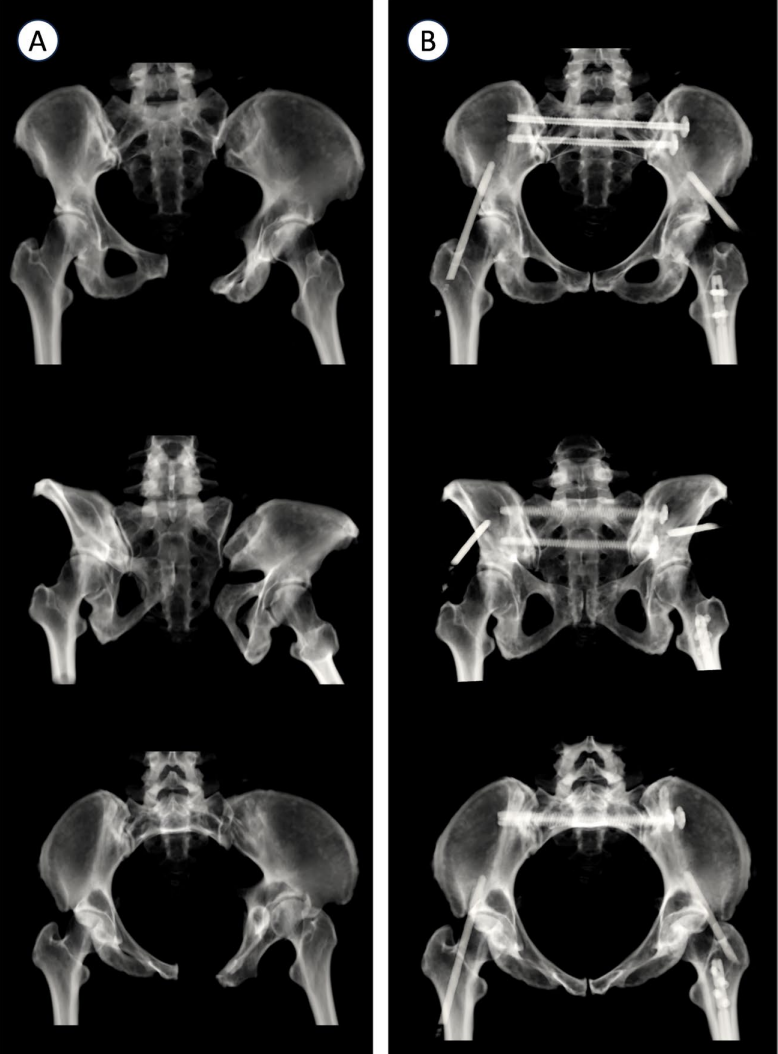

2、外固定器置入 :第一阶段是在两侧无名骨(受伤侧和未受伤侧)置入固定针。每个半骨盆采用双正交固定:额状面的髋臼上针和矢状面的 LC2 通道针。(图1a - 1b)此技术可增强头侧 / 尾侧复位控制并提高旋转稳定性。固定针设置如下:在标准前后位(AP)视图下,将额状面的髋臼上针置于髋臼眉弓上方,直达无名骨内板且避免损伤关节。对于 LC2 针,可用泪滴视图或 "Teepee" 视图(出口闭孔位)观察通道,但由于器械操作干扰,不一定需获取该视图。因针长及透视下对准通道轴有难度,故采用两个正交视图。髂骨视图用于确定髂前下棘(AIIS)的进针点,并引导头尾轨迹,目标是坐骨大切迹头侧。入口闭孔视图则确保针不置于盆内或盆外。

共纳入 15 例患者,其中男 10 名,女 5 名,平均年龄 35 岁,平均 BMI 为 30。骨折类型包括侧方挤压型(LC)3 型骨折 5 例,前后挤压型(APC)3 型骨折 4 例,LC 2 型骨折 2 例,垂直剪切损伤 4 例。平均手术时间为 130 分钟,术后影像显示平均最大移位为 5.4 毫米,平均不对称性为 3.7 毫米(表1)。总体而言,大多数病例患者实现优秀或良好复位。